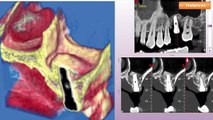

Convegno di diagnostica per immagini radiologiche

Convegno di interventistica radiologica svoltosi ad Andria.

Diagnostica per immagini, così la tecnologia CBCT l'ha trasformata